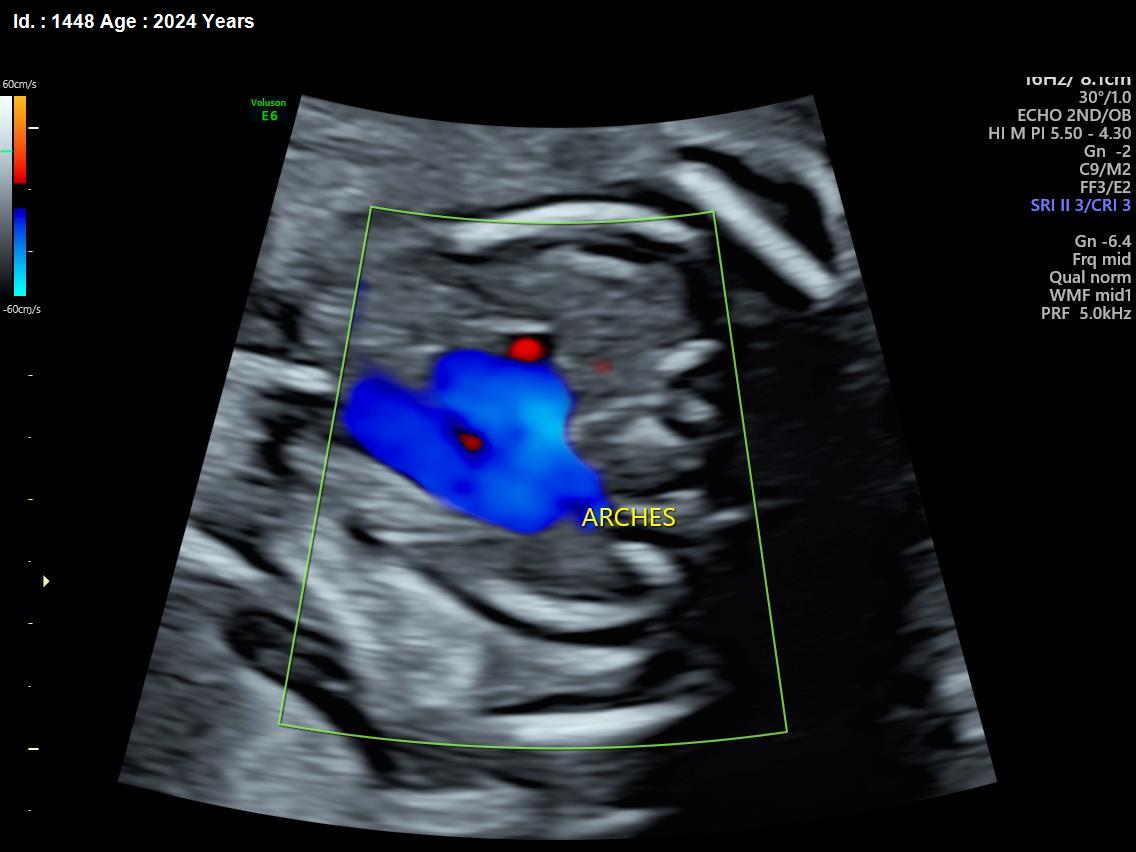

It is a test similar to ultrasound. It allows the doctor to see structure and function of the baby’s heart in detail. It also enables the doctor to see blood flow through fetal heart and cardiac rhythm. The scan is done by a radiologist or a fetal medicine specialist.

A fetal echocardiogram focuses specifically on the fetal heart, providing a detailed examination of its structure and function. In contrast, a standard ultrasound assesses overall fetal development and growth.